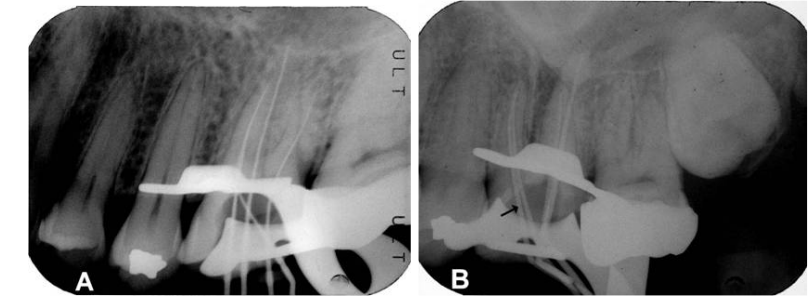

10.比較下圖兩張X光片中的第一小臼齒,並選出最恰當的敘述? (A)該牙齒接受根管治療及根尖區手術,根尖區組織修復(repair) (B)該牙齒接受根管治療及根尖區手術,牙根處出現外生骨贅(exostosis) (C)該牙齒接受根管治療,併發齒頸部吸收(cervical resorption) (D)該牙齒接受根管治療,牙根尖發生取代性吸收(replacement resorption)

19.下列為治療同顆牙齒拍攝不同角度的X光片。相對於A圖,B圖中第一大臼齒拍攝的角度以及箭頭所指的根管名稱為何? (A)從近心側往遠心側拍攝,箭頭所指根管為近心頰側根管(MB canal) (B)從近心側往遠心側拍攝,箭頭所指為第二近心頰側根管(MB2 canal) (C)從遠心側往近心側拍攝,箭頭所指為近心頰側根管(MB canal) (D)從遠心側往近心側拍攝,箭頭所指為第二近心頰側根管(MB2 canal)